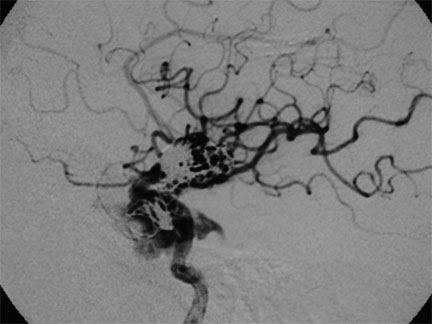

CASO 1 : Embolización de Fístula Carótidocavernosa que se desarrolló a partir de un traumatismo craneal

Antes del tratamiento por embolización de fístula carótidocavernosa. Observe la severa dilatación de la vena oftálmica, responsable de la congestión ocular